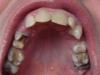

igor1603 Опубликовано 4 июня, 2009 Автор Поделиться Опубликовано 4 июня, 2009 не знаю получилось или нет..но попробую вставить...вопрос тот же...предлагают на 4ку залечить каналы (4тыщ)..и культевую вкладку..за 12 тыщ....тройка отсутствует...думаю над имплантом....5ка врач сказала корень сгнил....со временем придется удалять....а за 4ку бороться....у меня вопрос что делать в данной ситуации....вопрос пока именно по этим зубам...нервная система расшатана..сам знаю что других проблем море..но денег не так много.. Ссылка на комментарий

Sir Edward'S Опубликовано 5 июня, 2009 Поделиться Опубликовано 5 июня, 2009 не знаю получилось или нет..но попробую вставить...вопрос тот же...предлагают на 4ку залечить каналы (4тыщ)..и культевую вкладку..за 12 тыщ....тройка отсутствует...думаю над имплантом....5ка врач сказала корень сгнил....со временем придется удалять....а за 4ку бороться....у меня вопрос что делать в данной ситуации....вопрос пока именно по этим зубам...нервная система расшатана..сам знаю что других проблем море..но денег не так много.. 1-желательно фото полости рта2- 4 зуб разрушен до десны или под десну? Ссылка на комментарий

igor1603 Опубликовано 8 июня, 2009 Автор Поделиться Опубликовано 8 июня, 2009 вопрос к Нск Андрею и Sir Edward"S можно ли мне делать на 4ку культевую вкладку?....нормальный ли у меня корень?..что то врач неуверенно ответила....а я смотрю там черное и переживаю может там сгнило все....а 16тыщ выкинешь...разместил здесь потому что она сказала что эту культевую вкладку делает ПРОТЕЗИСТ Ссылка на комментарий

Bier Опубликовано 9 июня, 2009 Поделиться Опубликовано 9 июня, 2009 делается все просто - убирается весь кариес, а потом оценивается можно ли зуб сохранить.кстати 5ка, гораздо хуже по снимку выглядит. Правда снимок не четкий. Ссылка на комментарий

Нск Опубликовано 9 июня, 2009 Поделиться Опубликовано 9 июня, 2009 На 4-ку просится вкладка с коронкой, но, перед этим необходимо корневое лечение, т.е., "иголками" доктор прочищает и пломбирует каналы. Ссылка на комментарий